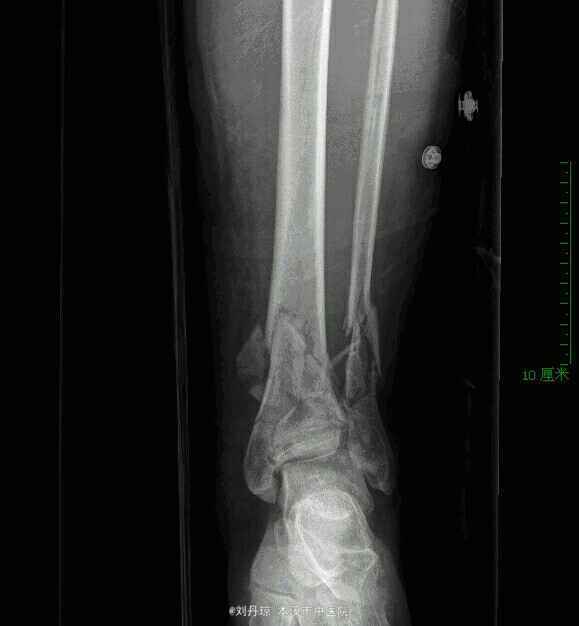

患者男性51岁左踝外伤后刺痛、肿胀、活动受限2小时。病史:患者2小时前从10米高处坠落,左踝摔伤,伤后来诊,门诊医师以左踝pilon骨折诊断收入院。

左踝关节粉碎骨折,左踝pilon骨折。